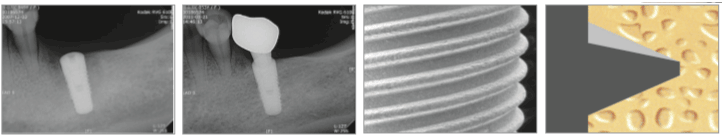

1. Platform váltás

A platform váltás csökkenti a csonvesztés lehetőségét, ezzel növelve a terheléselosztást, és végül megőrizve a marginális csöntszöveteket.

2. Sima váll

Sima felületű implantátum nyak segítségével biztonságosan könnyen beállítható, korrigálható a behelyezett implantátum magassága.

3. Optimális vágóél

Megakadályozza a víz felszívódását a kéregállományba a bakteriális fertőzés és a csontleépülés megelőzéséért. A kúpos menettel ellátott implantátumtest ideális a terheléselosztásban, valamint anatómialilag is a legközelebb áll a foggyökér alakjához. A nagyobb stabilitásnak köszönhetően optimalizálja a szögeltérést a kortikális csont és az implantátum között.

4. Hermetikus lezárás

Az implantátum és a felépítmény közti hermetikus lezárás biztosítja a terhelés egyenletes eloszlását, és minimálisra csökkentve a mikro-mozgásokat és a csontvesztést.

5. Biztonságos vágó él

Minimalizálja a csont ellenállását behelyezéskor. Biztonságos és zavartalan implantátum behelyezést tesz lehetővé.

7. Kúpos vég kialakítása

Kisebb esély a perforációra

Kúpos kialakítás

"Root" formatervezés a jobb terheléseloszlásért ahol a csont kondíciója nem megfelelő, lehetővé téve egy gyorsabb és stabilabb műtéti rendszert, csökkentve a műtéti időt.

Optimális RBM felület

A felületi finomság 1,5 +-0.2 mikrométer, ami a legtökéletesebb érték az osszeointegrációhoz.

Dupla menetes dizájn

Kétbekezdéses menetkialakításnak köszönhetően csökken az implantátumbehelyezési idő.